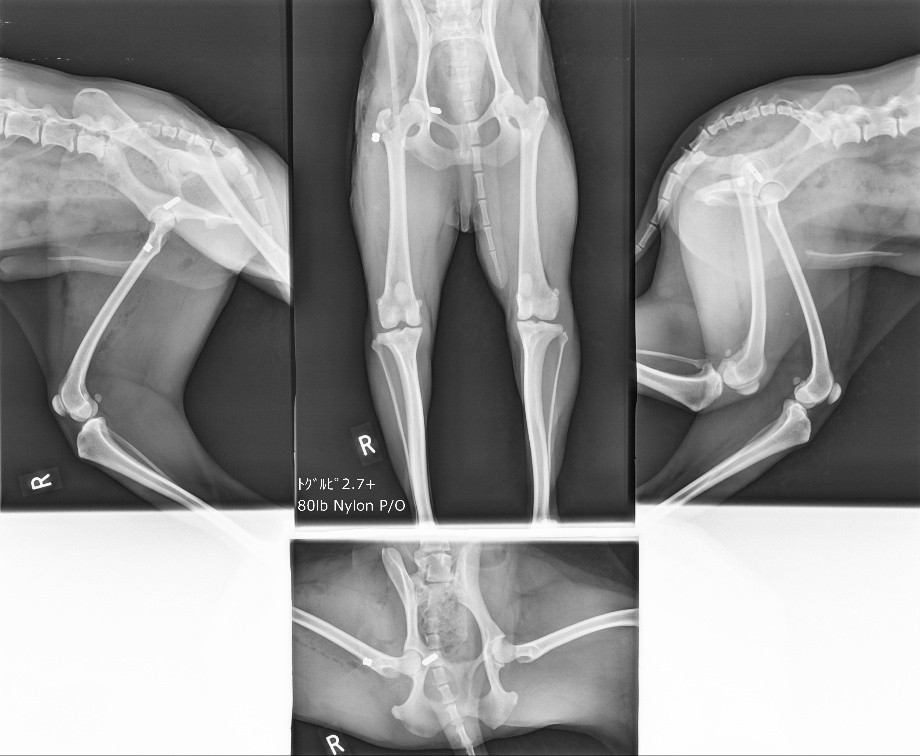

手術は無事成功し、術後はしっかりと関節が安定していることが確認できました。

術後のリハビリを経て、今では痛みもなくなり、しっかりと自分の足で歩けるようになりました。繰り返す脱臼の悩みから解放され、元気に過ごしてくれています。